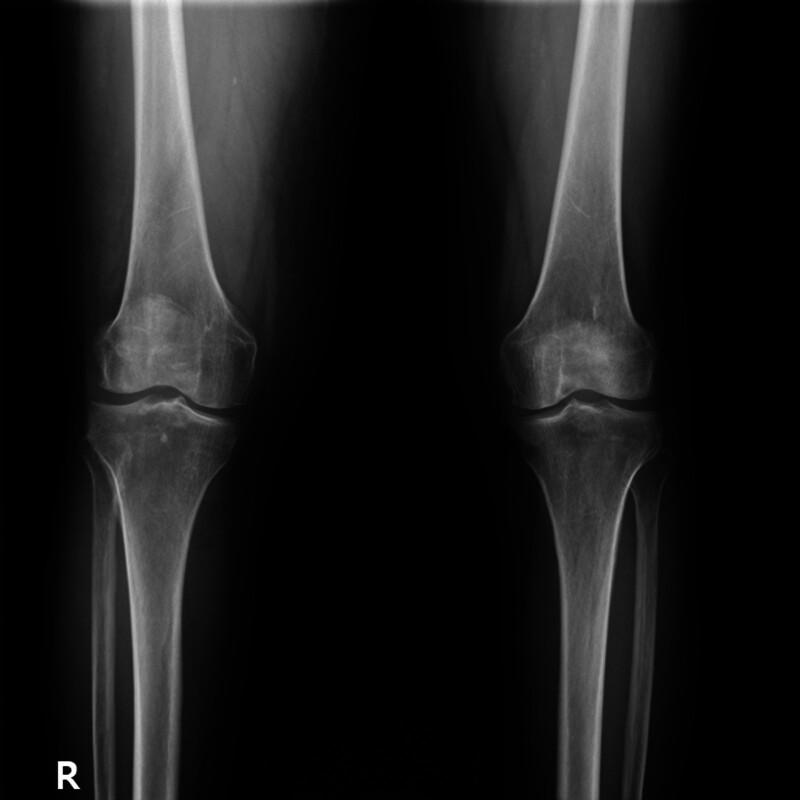

A post-kidney transplantation patient presented with lower extremity symptoms. Initial lumbar spine magnetic resonance imaging suggested foraminal stenosis and disc herniation. However, persistent symptoms and lack of clinical improvement prompted further investigation. A contrast-enhanced computed tomography revealed a retroperitoneal mass compressing the iliac vessels. Biopsy confirmed diffuse large B-cell lymphoma.

一名肾移植术后患者出现下肢症状。最初的腰椎磁共振成像提示椎间孔狭窄和椎间盘突出。然而,症状持续且缺乏临床改善促使进一步检查。增强计算机断层扫描显示一个压迫髂血管的腹膜后肿块。活检确诊为弥漫性大B细胞淋巴瘤。